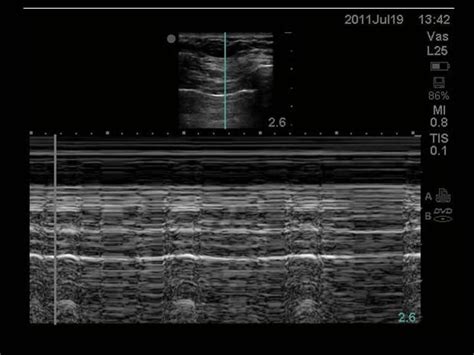

A pneumothorax separates the visceral and parietal pleura, eliminating normal lung sliding between these layers on lung us. Once you understand these basic lung ultrasound findings you will be able to interpret just about any lung ultrasound images. When m mode is used on a normal lung, the lung (and the air inside it) moves back and forth across this single ultrasound beam creating a picture that is often compared to a sandy beach. Unless the pneumothorax is loculated or there are adhesions, the gas moves freely within the thoracic cavity. There is normal lung sliding on the right side. Lung ultrasound pathology profiles such as pneumothorax, pneumonia, cardiogenic pulmonary edema, etc will have a different combination and distribution of these pathological lung ultrasound findings/signs. Nov 08, 2017 · primary spontaneous pneumothorax: 3 article feature images from this case Ein pneumothorax (gelber pfeil) mit noch geringer. To evaluate for pneumothorax with ultrasound, have the patient lay supine. In the supine trauma patient, this will typically be the anterior chest wall lateral to the sternum in the second intercostal space. Among 302 analyzable controls, 65 had absent lung sliding, 16 of them showed an a line sign, and none showed a lung point. Each site was scanned twice at each time point.

Ruling out a pneumothorax is the easy part for me, and it doesn't require much more than a quick visual inspection. Ultrasound can also allow semiquantitative assessment of pneumothorax size by assessing the position of the lung point. Once you understand these basic lung ultrasound findings you will be able to interpret just about any lung ultrasound images. · february 14, 2020 · 1 min read. Nov 08, 2017 · primary spontaneous pneumothorax: Ultrasound use may therefore obviate the need for ct in a majority of cases. Additionally, it can result in timely diagnoses specifically in neonatal pneumothorax. The probe should be oriented perpendicular to the ribs (usually marker dot towards the head). You can also use m mode, or motion mode, which provides an image showing tissue motion along a single ultrasound beam. Unless the pneumothorax is loculated or there are adhesions, the gas moves freely within the thoracic cavity. At its heart, the concept behind using ultrasound to evaluate for air in the space between the visceral and parietal pleura is straightforward. Ultrasound scans in all 43 examinable patients with pneumothorax showed absent lung sliding, 41 of 43 patients had the a line sign, and 34 exhibited a lung point. Ultrasound outperforms cxr in evaluation of pneumothorax in blunt trauma patients, but there cite this article as:

Nov 08, 2017 · primary spontaneous pneumothorax: Ultrasound outperforms cxr in evaluation of pneumothorax in blunt trauma patients, but there cite this article as: Lack of ionizing radiation and easy operation are benefits of this imaging technique. 1 traumatic pneumothorax is common in dogs, whereas spontaneous pneumothorax is relatively rare. In the supine trauma patient, this will typically be the anterior chest wall lateral to the sternum in the second intercostal space. When m mode is used on a normal lung, the lung (and the air inside it) moves back and forth across this single ultrasound beam creating a picture that is often compared to a sandy beach. To evaluate for pneumothorax with ultrasound, have the patient lay supine. A pneumothorax separates the visceral and parietal pleura, eliminating normal lung sliding between these layers on lung us. Among 302 analyzable controls, 65 had absent lung sliding, 16 of them showed an a line sign, and none showed a lung point. Since then there have been many studies that have shown bedside ultrasound can rapidly detect pneumothorax, helping avoid serious potential consequences (i.e. These are the thoracic radiographs: Thoracic ultrasound has more sensitivity than a supine chest radiograph (see: Identification of a lung point on lung us yields 100% specificity for pneumothorax (58).